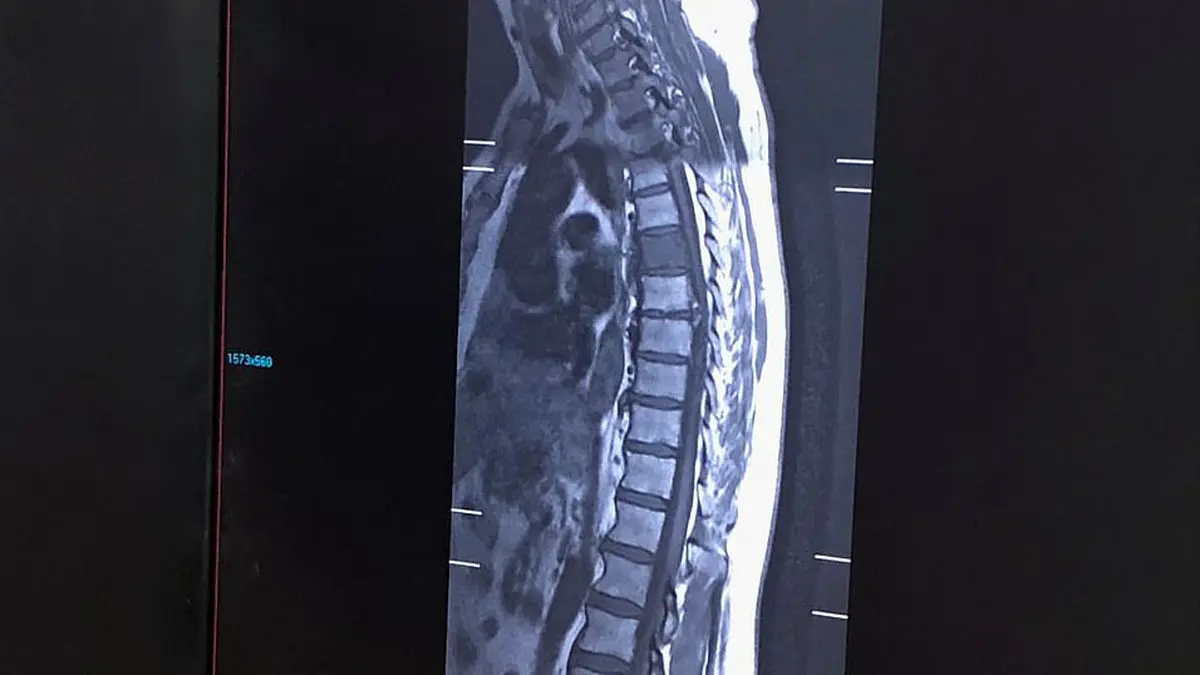

به گزارش گروه ترجمه رکنا، مرد 70 ساله ای که با بیماری سرطان مبارزه می کرد با دیدن عکس یک سگ در تصویر اشعه ایکس ستون فقراتش شوکه شد.

بیمار پیتر کوانگ 70 ساله این عکس باورنکردنی را در بیمارستان والتون لیورپول انگلیس گرفته و اعضای خانواده این مرد که 20 سال است با بیماری سرطان مری زندگی کرده است با دیدن سگ در عکس شگفت زده شدند.